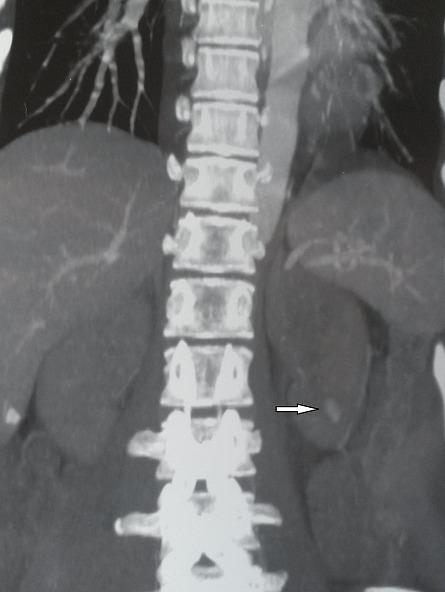

We report the treatment of a bleeding renal pseudoaneurysm by angio-embolization. A 21 years old woman developed macroscopic haematuria following renal biopsy. Renal angio-scan showed a 1.4 cm renal pseudoaneurysm in the left kidney. The presence of pseudoaneurysm was confirmed by selective renal angiography. Successful embolization was performed using gelatine sponge particles.

我们报告了一例通过血管栓塞治疗出血性肾假性动脉瘤的病例。一名21岁女性在肾活检后出现肉眼血尿。肾脏血管扫描显示左肾有一个1.4厘米的肾假性动脉瘤。通过选择性肾血管造影证实了假性动脉瘤的存在。使用明胶海绵颗粒成功进行了栓塞。